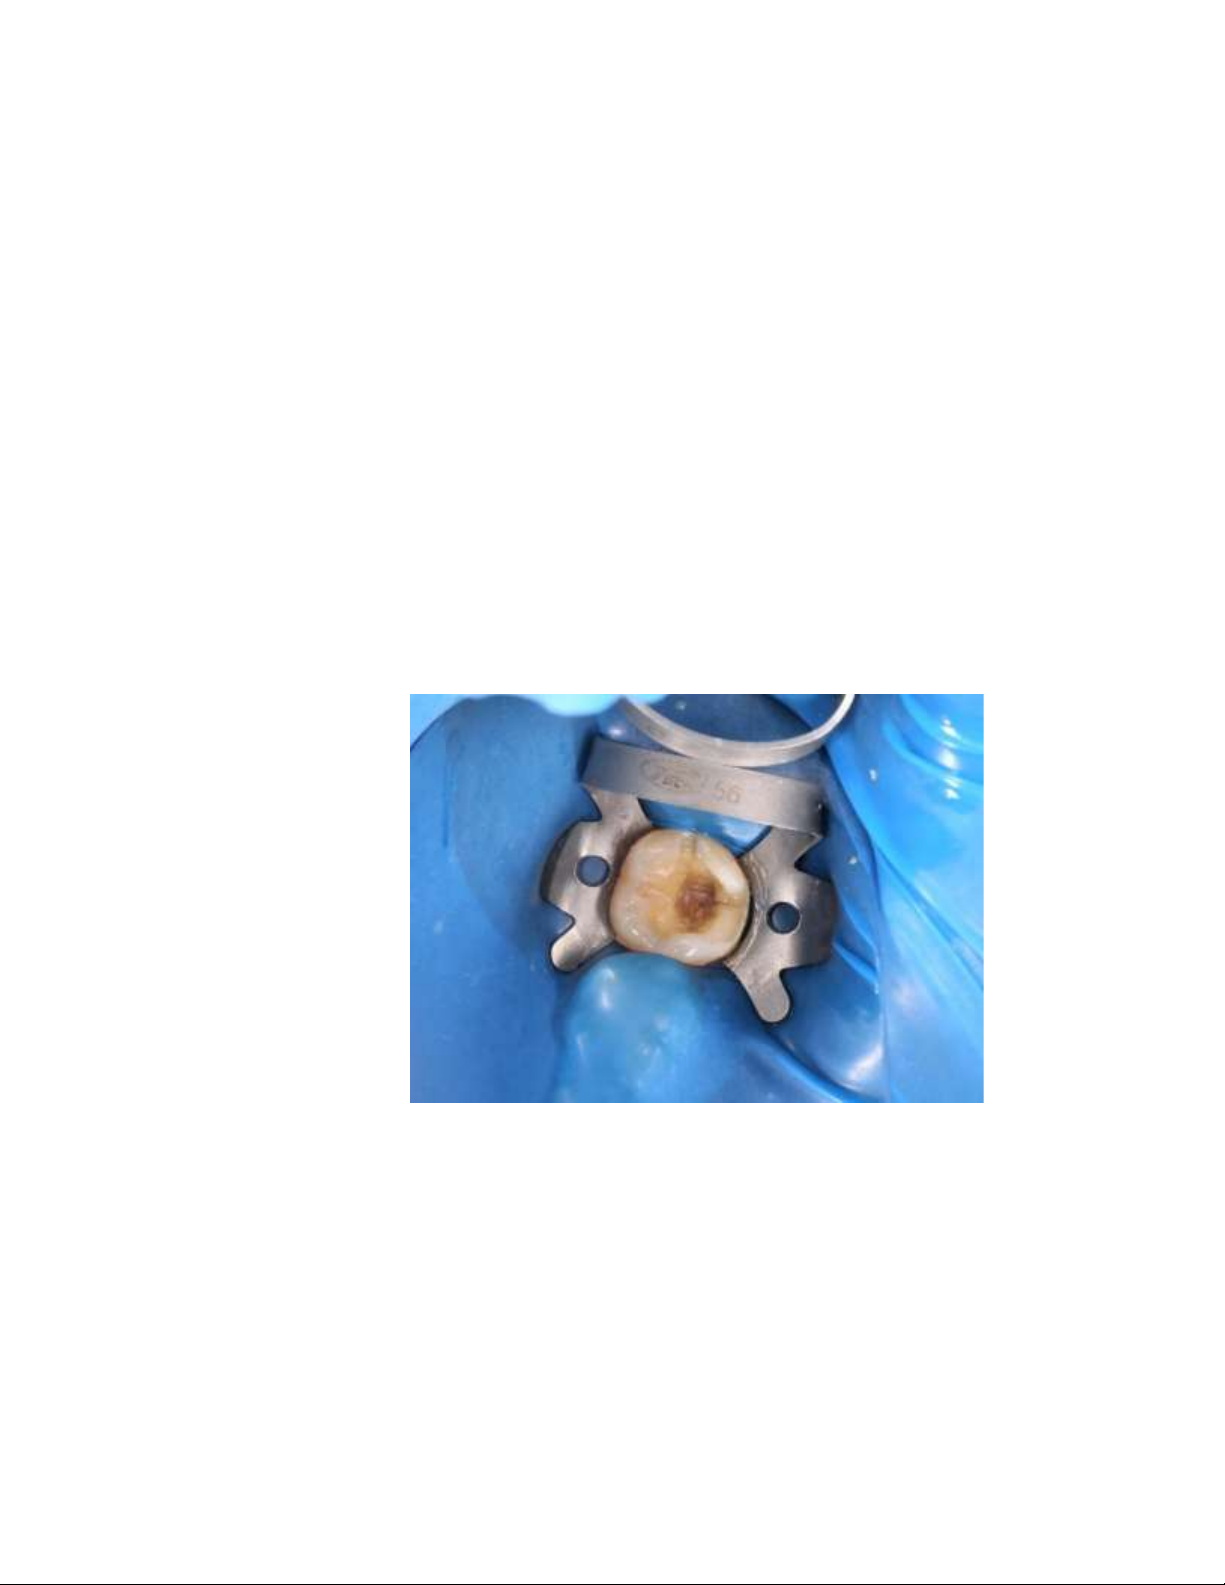

Đê cao su là một tấm cao su latex hoặc không latex mỏng, phẳng được đục lỗ, giữ bởi clamp và

khung cho phép răng/các răng được bộc lộ ra qua đó, trong khi các răng còn lại được che phủ bởi tấm cao su.

Hình 1. Đặt đê cao su trên người bệnh